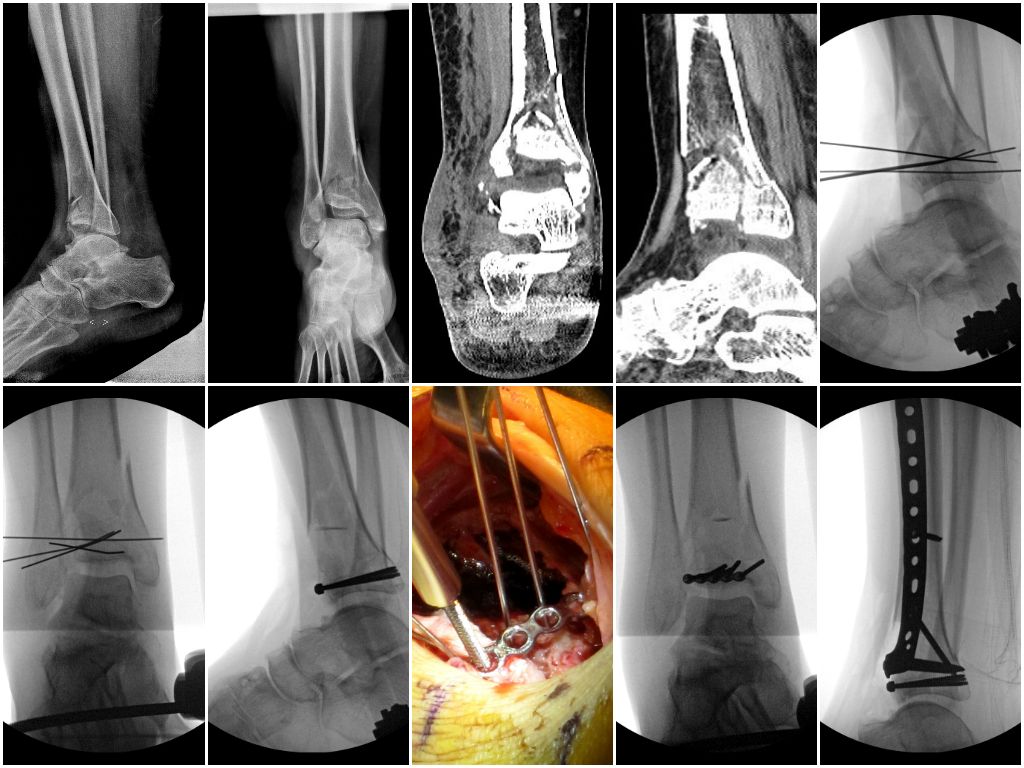

Мини-винты: длинные и прочные. D = 2.0 мм (можно также 1.8/2.4/2.5 мм), длина (10-40+ мм). Где можно достать?

Особенно интересуют длинные, больше 30 мм, этим и обуславливаются требования к прочности винта.

Те, которыми мы обычно пользуемся от локального украинского производителя, имеют длину до 23 мм, длиннее не делают из-за довольно низкой прочности.Зачем, спросите вы, такие длинные мини-винты?А вот затем, что иногда, их достаточно удобно можно использовать для фиксации суставной поверхности, в особенно если фрагменты перелома - мелкие. Можно провести субхондрально. Попробовав зарубежом, хочется иметь такую опцию и у нас.

О, пардон не обратил внимание на диаметр. А разве в примере не 3,5 мм винты?